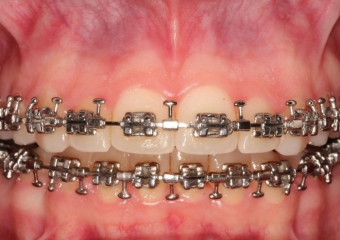

Mordida inicial

Mordida após a cirurgia